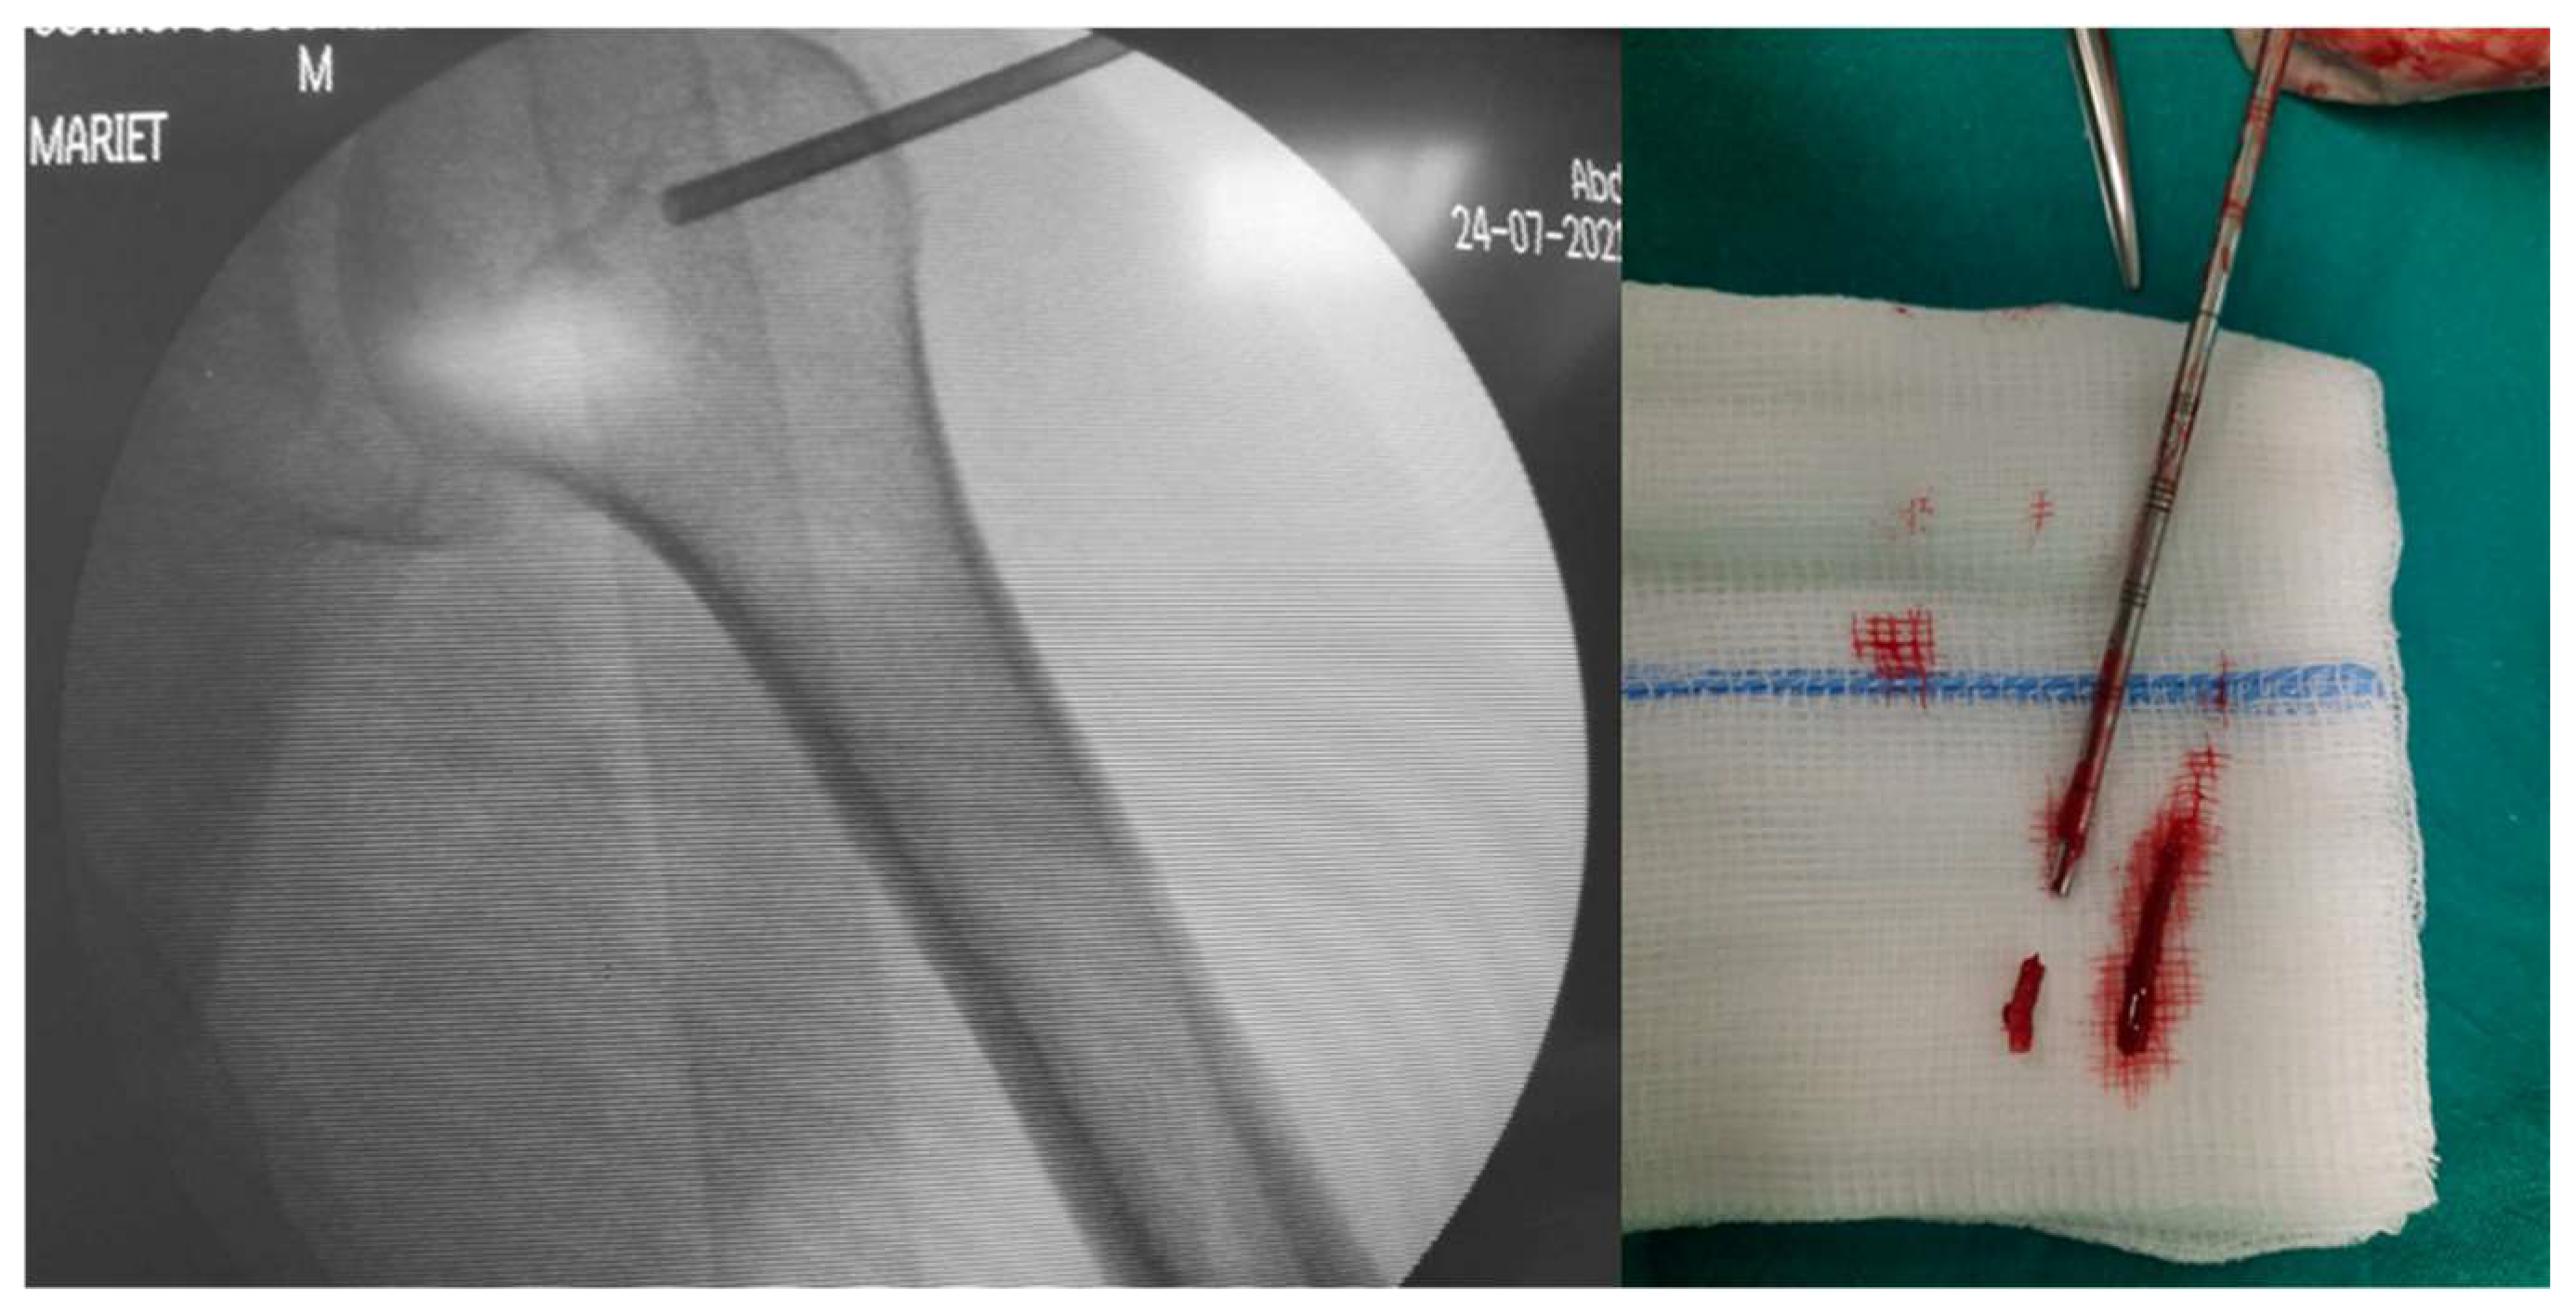

2.2. Core-Needle Biopsy

| Closed biopsy | The gold standard, especially if guided. Minimally invasive, high accuracy (no difference with open biopsy), cost effective, rare complications (<11%). |